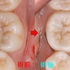

近心根にはパフォーレーション 手付かずの遠心根には破折線が見られ、

患者さんにどうします!?遠心根はまず残せない、近心根は残すことが出来るがパフォーレーションの位置的に長く持たない可能性がある。

不思議なんですが、遠心根は根管治療していないにも関わらず折れてきている。

イメージ的に根管治療を行い中を削って歯を弱体化させている近心根が折れるならまだ分かるのですが・・・

患者さんと話し合い、近心根はヘミセクションをして残す 遠心根は抜歯

右下7の所には親知らずの移植と計画をしました。

2026 EEdental FUD (3).jpg

この後遠心根抜歯